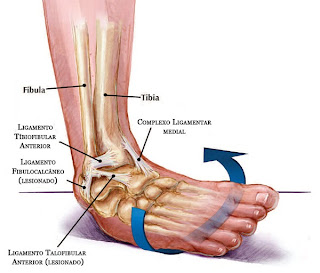

O entorse de

tornozelo é uma lesão muito comum entre atletas e esportistas, mas também pode

ocorrer ao andar, correr ou saltar.

É uma lesão que

ocorre pelo movimento forçado em alavanca do tornozelo para dentro em direção a

linha media do corpo, ultrapassando o limite de resistência dos ligamentos, e

irá resultar em danos estruturais no local.

Temos dois

tipos de entorses: o entorse por distensão ligamentar e o entorse com fratura,

este é mais grave pois ocorre rompimento dos ligamentos com tração e fratura

das estruturas.